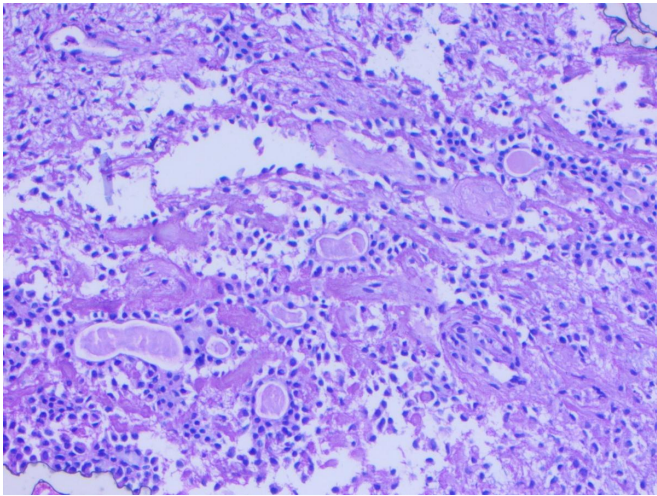

A 71-year-old female presented at Bankers Superspeciality Hospital complaining of swelling over the right side of the face and upper neck region, with localised swelling over the sternum. She was asymptomatic 5 months back as she gradually noticed swelling over her right side of her face and upper neck region, which gradually increased in size. In the past (2018), she had surgery at a local hospital, query for parotid surgery; no documents were available ( surgery note and histopathological report). On inspection and palpation, 8*7cm hard proliferative, lobulated growth present over the right side upper neck region, not fixed to underlying structures, crossing midline of the face with no ulceration present over skin (Image 1). No neck nodes were palpable. No sign of facial palsy present. Localised mass of 6*5cm was present over the right side sternum, which was fixed to the underlying bone (Image 2). No skin ulceration was present over sternum region and no axillary nodes were palpable. The performance status of the patient was ECOG 1. Computed tomography of Neck and chest (Plain + Contrast) suggestive of large heterogeneously enhancing lobulated solid cystic lesion seen in right submandibular and upper internal jugular regions and right submental region anterior to right sternocleidomastoid muscle, size of 94(W)*76(AP)*79.6(CC)mm, with mild compression on right IJV. Approx 78*75*92mm soft tissue lesion involving sternum causing osteolytic destruction extending into the anterior mediastinum displacing heart and other structures posteriorly. A few variable-sized soft tissue density nodules scattered throughout both lungs (Image 3 & Image 4). Trucut Biopsy from Right submandibular region s/o pleomorphic adenoma ( composed of epithelial tubules and myoepithelial cells in abundant chondromyxoid stroma) (Image 5 & Image 6). Trucut Biopsy from sternal mass suggestive of malignant tumor, likely to be sarcoma, chondrosarcoma is a possibility. Further Immunohistochemistry was done which suggestive of lesional cells with chondroid type appearance and matrix with positive for AE1/3, CK7 and S100 with KI-67 2-3% favouring Benign metastasizing pleomorphic adenoma (Image 7 & Image 8). PETCT scan was done, which suggestive of FDG avid heterogenously enhancing lobulated soft tissue mass involving right submandibular and submental region 8.6(AP)*7.3(TS)*8.9(CC) ; SUV max 8.6. Medially involving the Right submandibular gland Indenting onto right SCM and strap muscles, Superioly lesion is infiltrating inferior lobe of right parotid gland, overlying skin is involved with no obvious erosion. FDG avid lytic destructive lesion are noted involving sternum, left fifth rib, D12 and L3 vertebrae. Sternal lytic destructive lesion is present with soft tissue compenent with calcification of 8.2*7.2*10.5cm; SUV max 5.9. Soft tissue component is extending into anterior mediastinum and is seen infiltrating right middle lobe lung parenchyma. Left fifth rib is assosciated with  FDG avid enhancing soft tissue component 2.6*2.3cm; SUVmax 6.5 (Figure 9). On PETCT Scan report with skeletal metastasis, in multidisciplinary tumor board discussion, the case was discussed and decided to give palliative chemotherapy.

Figure 5: Ductal elements and background chondromyxoid stroma and myoepithelial cells

Figure 6: Bone with background PA